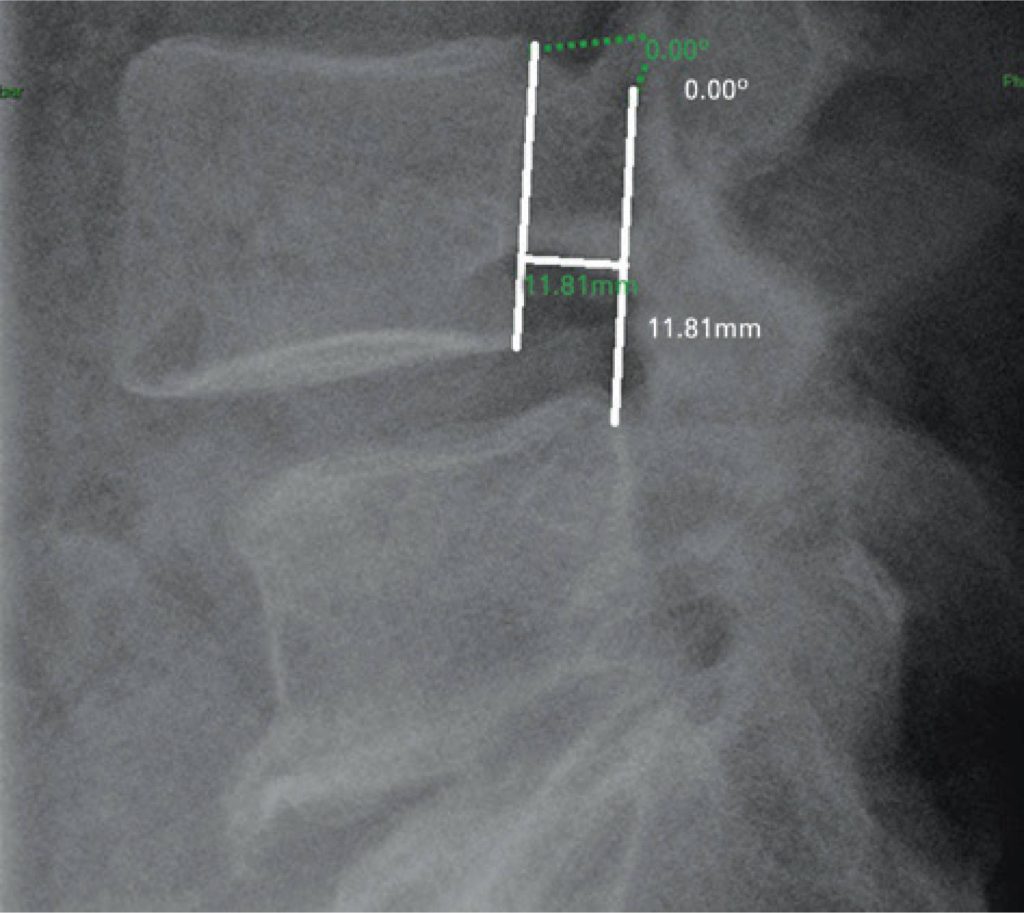

Measurements of the dynamic radiographs of the lumbar spine in lateral view were performed, evaluating the anterior translation and the angulation among the vertebral bodies. The tests were evaluated at workstations of the organization, through the Carestream Health Vue RIS (PACS), version 11.0.12.14 Inc. 2009© system.

Agreement in detecting cases of radiographic instability among the observers varied from 88.1 to 94.4%, and the agreement coefficients AC1 were all above 0.8, indicating excellent agreement.

The interobserver analysis performed among orthopedic surgeons with different levels of training in dynamic radiographs of the spine obtained high reproducibility and agreement. However, some factors, such as the manual method of measurement and the presence of vertebral osteophytes, might have generated a few less accurate results in this comparative evaluation of measurements.